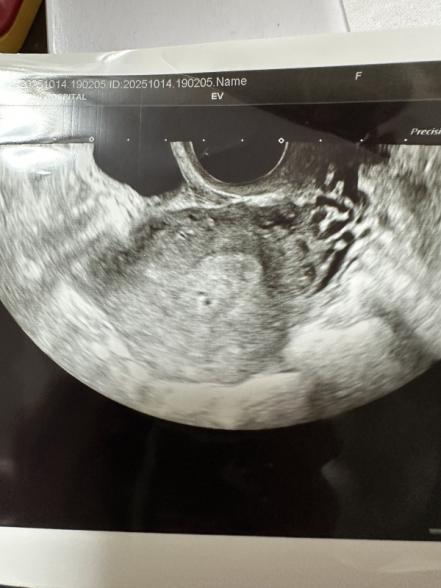

昨日日中に赤茶色のおりものが出て不安になり急遽5w2dで産婦人科に初診を受けに行ってきました。

経膣エコーで少しグリグリするとすぐ胎嚢らしきものは見えたのですが、先生も『う〜ん、多分これだと思うけどまだ小さくてね〜…』と言うくらい小さかったです。

大きさすら測ってもらえませんでした。

5w2dでは皆さん割としっかり胎嚢が見えているし、私自身1人目妊娠のときはしっかり見えたので今回成長が遅いのではと不安です。